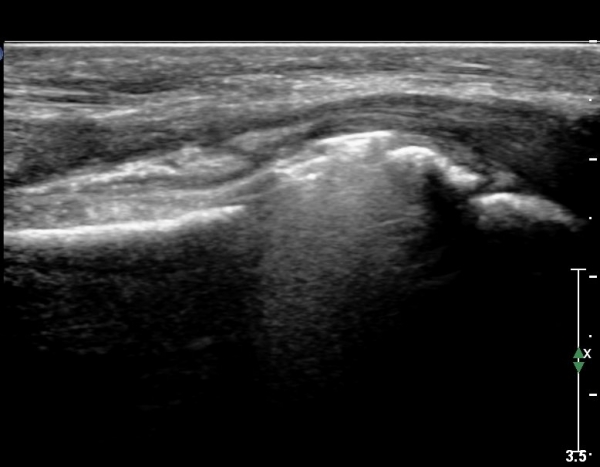

¾Æ·§ÆÈ »óºÎ Ⱦ´Ü¸é°Ë»ç¿¡¼­ Àü°ñ°£ ½Å°æ Áö¹è¸¦ ¹Þ´Â FPL, FDP ¿¡¼­ ½Å°æ¸¶ºñ ¼Ò°ß(°í¿¡ÄÚ ±ÙÀ§Ãà)À»

º¸ÀÌÁö ¾ÊÀ½(»çÁø 1)